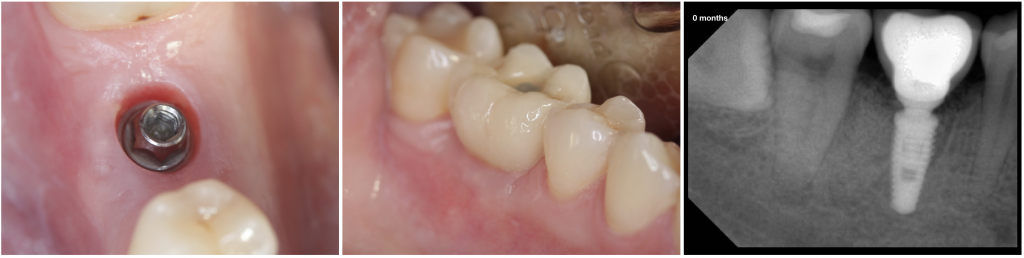

Fig. 2- Healing after 2 months, the definitive restoration was delivered.

During the observation period (12 months), the four implants were osseointegrated, and functional, mechanical or biological complications were not reported. The volume of the soft tissues and the horizontal ridge were lower than in the initial situation. However, the radiographic controls showed bone over the implant platform.

Post-surgical instructions were provided, including a soft diet for one week. During the healing period (12 weeks), two definitive abutments were removed because were too high so they were replaced by shorter ones. After that, the abutments were never removed, and the impressions were taken with standard or custom open trays and addition silicones.